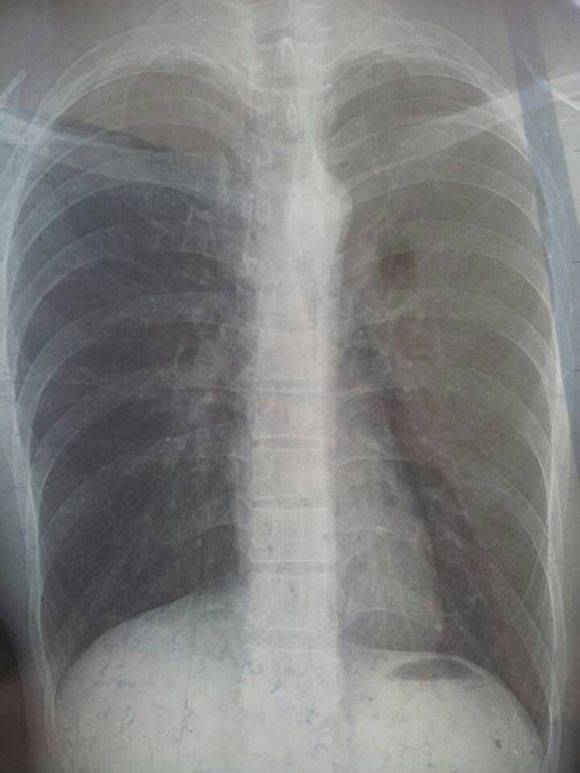

依靠胸片停药 草率啊. 我胸片都是心肺未见明显异常 拍ct就是有病灶 还有个小空洞